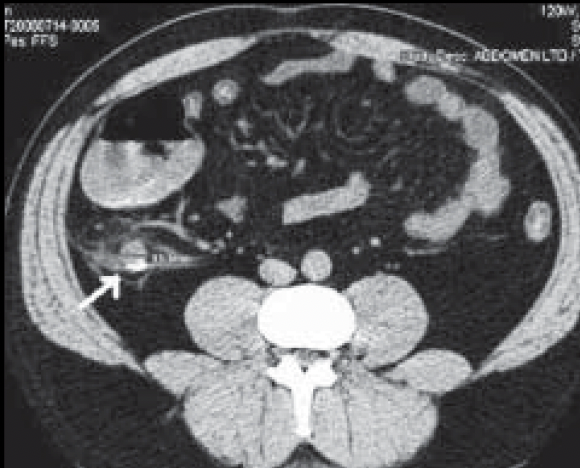

Mejor método dx adultos

TC

APENDICE RETROCECAL

SE VE GRASA SUCIA, APENDICOLITO, REALCE CON CONTRASTE